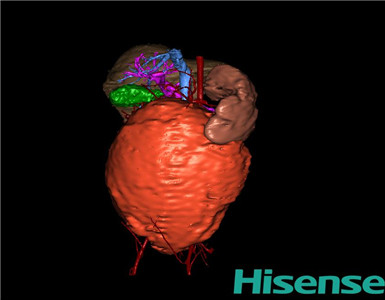

CT结果输入海信CAS系统后行3D重建及手术规划后,于2016-5-5全麻下行“腹膜后肿物切除术”手术治疗:

将0.625mm双源薄层CT资料的静脉期和动脉期Dicom格式文件导入海信CAS系统。

通过调节窗宽窗位调整CT序号,对肿瘤,肝脏,胆囊,下腔静脉,肿瘤,肝动脉、门静脉及肝静脉等进行三维重建;系统自动计算肿瘤体积和肝脏体积。

模拟手术操作,自动计算切除肿瘤体积。肝脏体积为425.6ml,肿瘤体积为971.8ml,肿瘤体积为肝脏体积的2.28倍,通过比对1-2岁正常肝脏体积为392.13±72.67ml,通过术前模拟手术,精准判断切除范围。

术前三维重建:

重建图片